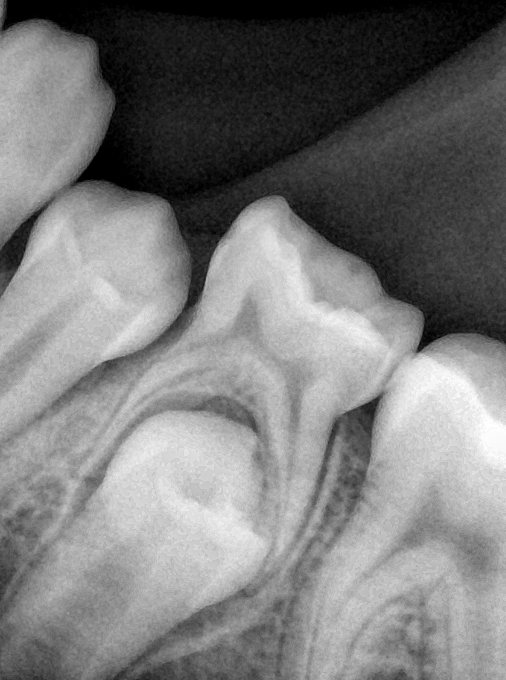

CR/DR 牙齿分割阶段记录

当前进展

- 完成了 CR/DR 牙齿相关分割训练

- 当前结果已经达到阶段预期,但仍有细节问题需要继续处理

相关测试

遇到的问题

- 训练过程中出现过 mask 下移问题

- 部分结果会出现 box 填充异常

- mask 边缘仍然有比较明显的锯齿感

参考

第二版算法问题测试